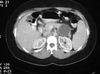

30 y.o. lady w/ epigastric pain + vomiting x 8 hours

Ultrasound gallbladder

CT abdomen:

(1) What next?

Endoscopic retrograde cholangiopancreatography

lesions obstructing the ampulla of vater or pancreatic duct should be excluded by ERCP.

This is most likely a pseudocyst.

A HIDA scan is for cholecystitis.

If nonsurgical drainage is contemplated, it is important to elucidate the anatomy of the pancreatic duct beforehand. This may be done via endoscopic retrograde cholangiopancreatography (ERCP) or magnetic resonance imaging (MRI)